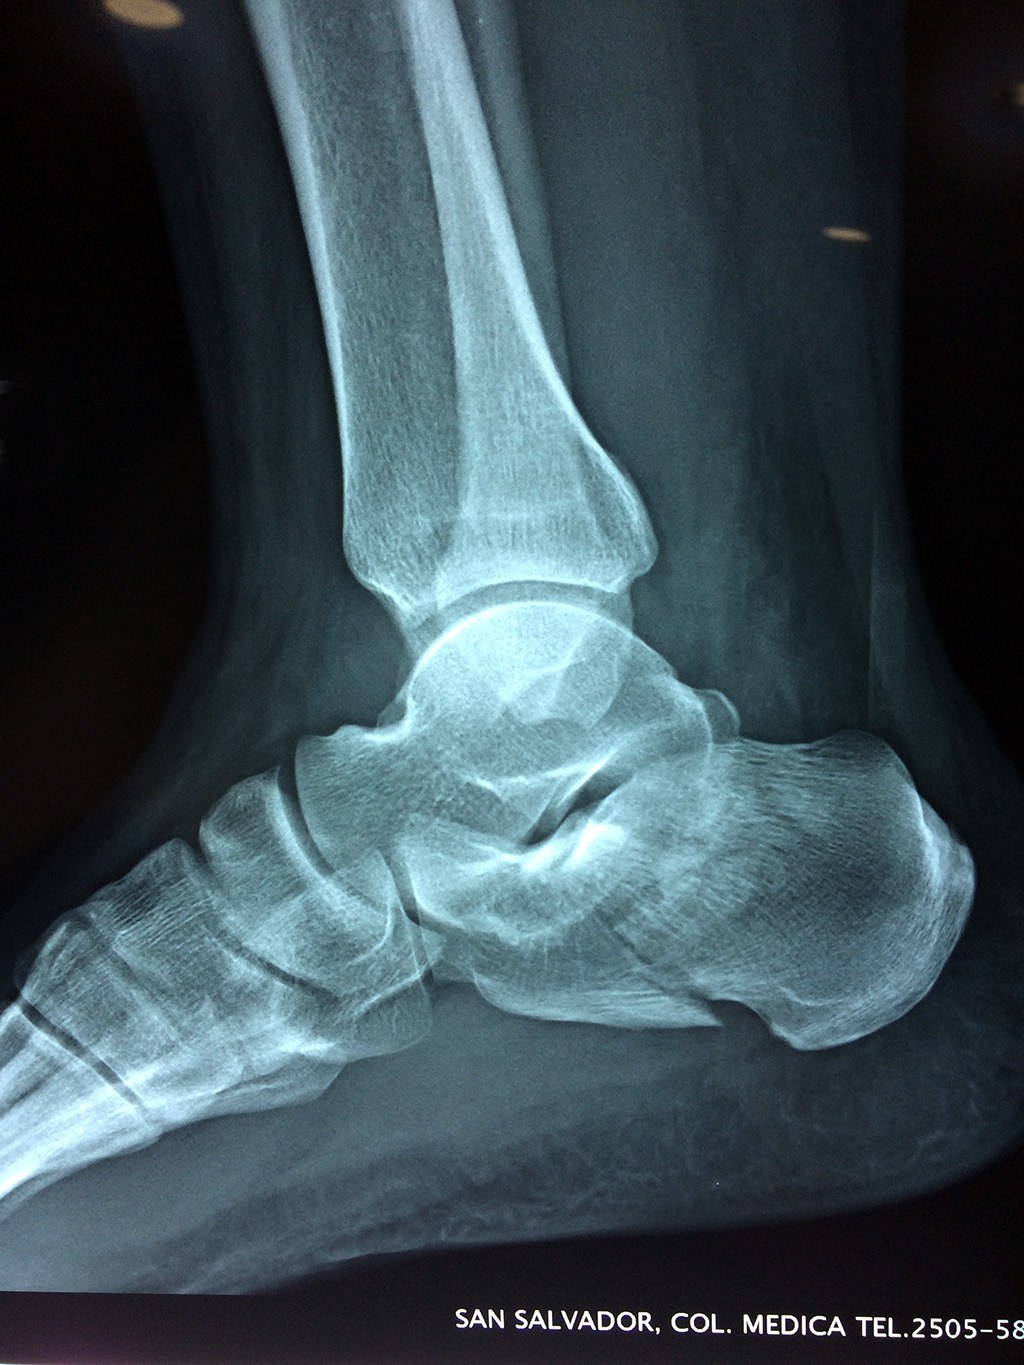

El calcáneo (del latín Os calcis) es un hueso del pie (tarso), corto, asimétrico, de forma cúbica irregular, con seis caras: superior e inferior, laterales y anterior y posterior, de las cuales dos son más o menos articulares.

Este hueso constituye el talón del pie. Se encuentra en la parte inferior de la primera fila del tarso. Se articula con el astrágalo por arriba y con el cuboides por delante. Constituye el primer punto de apoyo del pie durante la marcha, situándose en una de las zonas peor irrigadas del cuerpo y protegido plantarmente por la almohadilla plantar de tejido adiposo, con función amortiguadora.

En su cara posterior recibe la inserción del tendón más plantar, implicada en diversas enfermedades como la fascitis o el espolón calcáneo. La posición del calcáneo en relación al astrágalo (articulación subastragalina) y al suelo determinan la posición de retropié en varo, en valgo o neutra.

Los retropiés varos y sobre todo, los retropiés valgos, son responsables de distintas enfermedades del aparato locomotor y contribuyen a que aparezcan alteraciones de la marcha normal fisiológica, con consecuencias clínicas importantes (dolor, sobrecargas, aplanamiento, fatiga muscular, juanetes, etc.) tanto a nivel de pie como a nivel del miembro inferior.